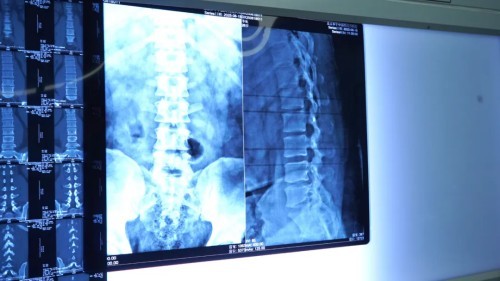

手术团队首先在C型臂X光机透视引导下进行精准穿刺定位,建立工作通道。在高清内镜的显示下,患者椎管内的病变情况一目了然:增厚的韧带、增生的骨质严重占据了椎管空间,而巨大的椎间盘突出物更是将神经根紧紧压迫,出现明显的充血和水肿。这正是导致李先生(化名)剧烈疼痛和麻木的“元凶”。